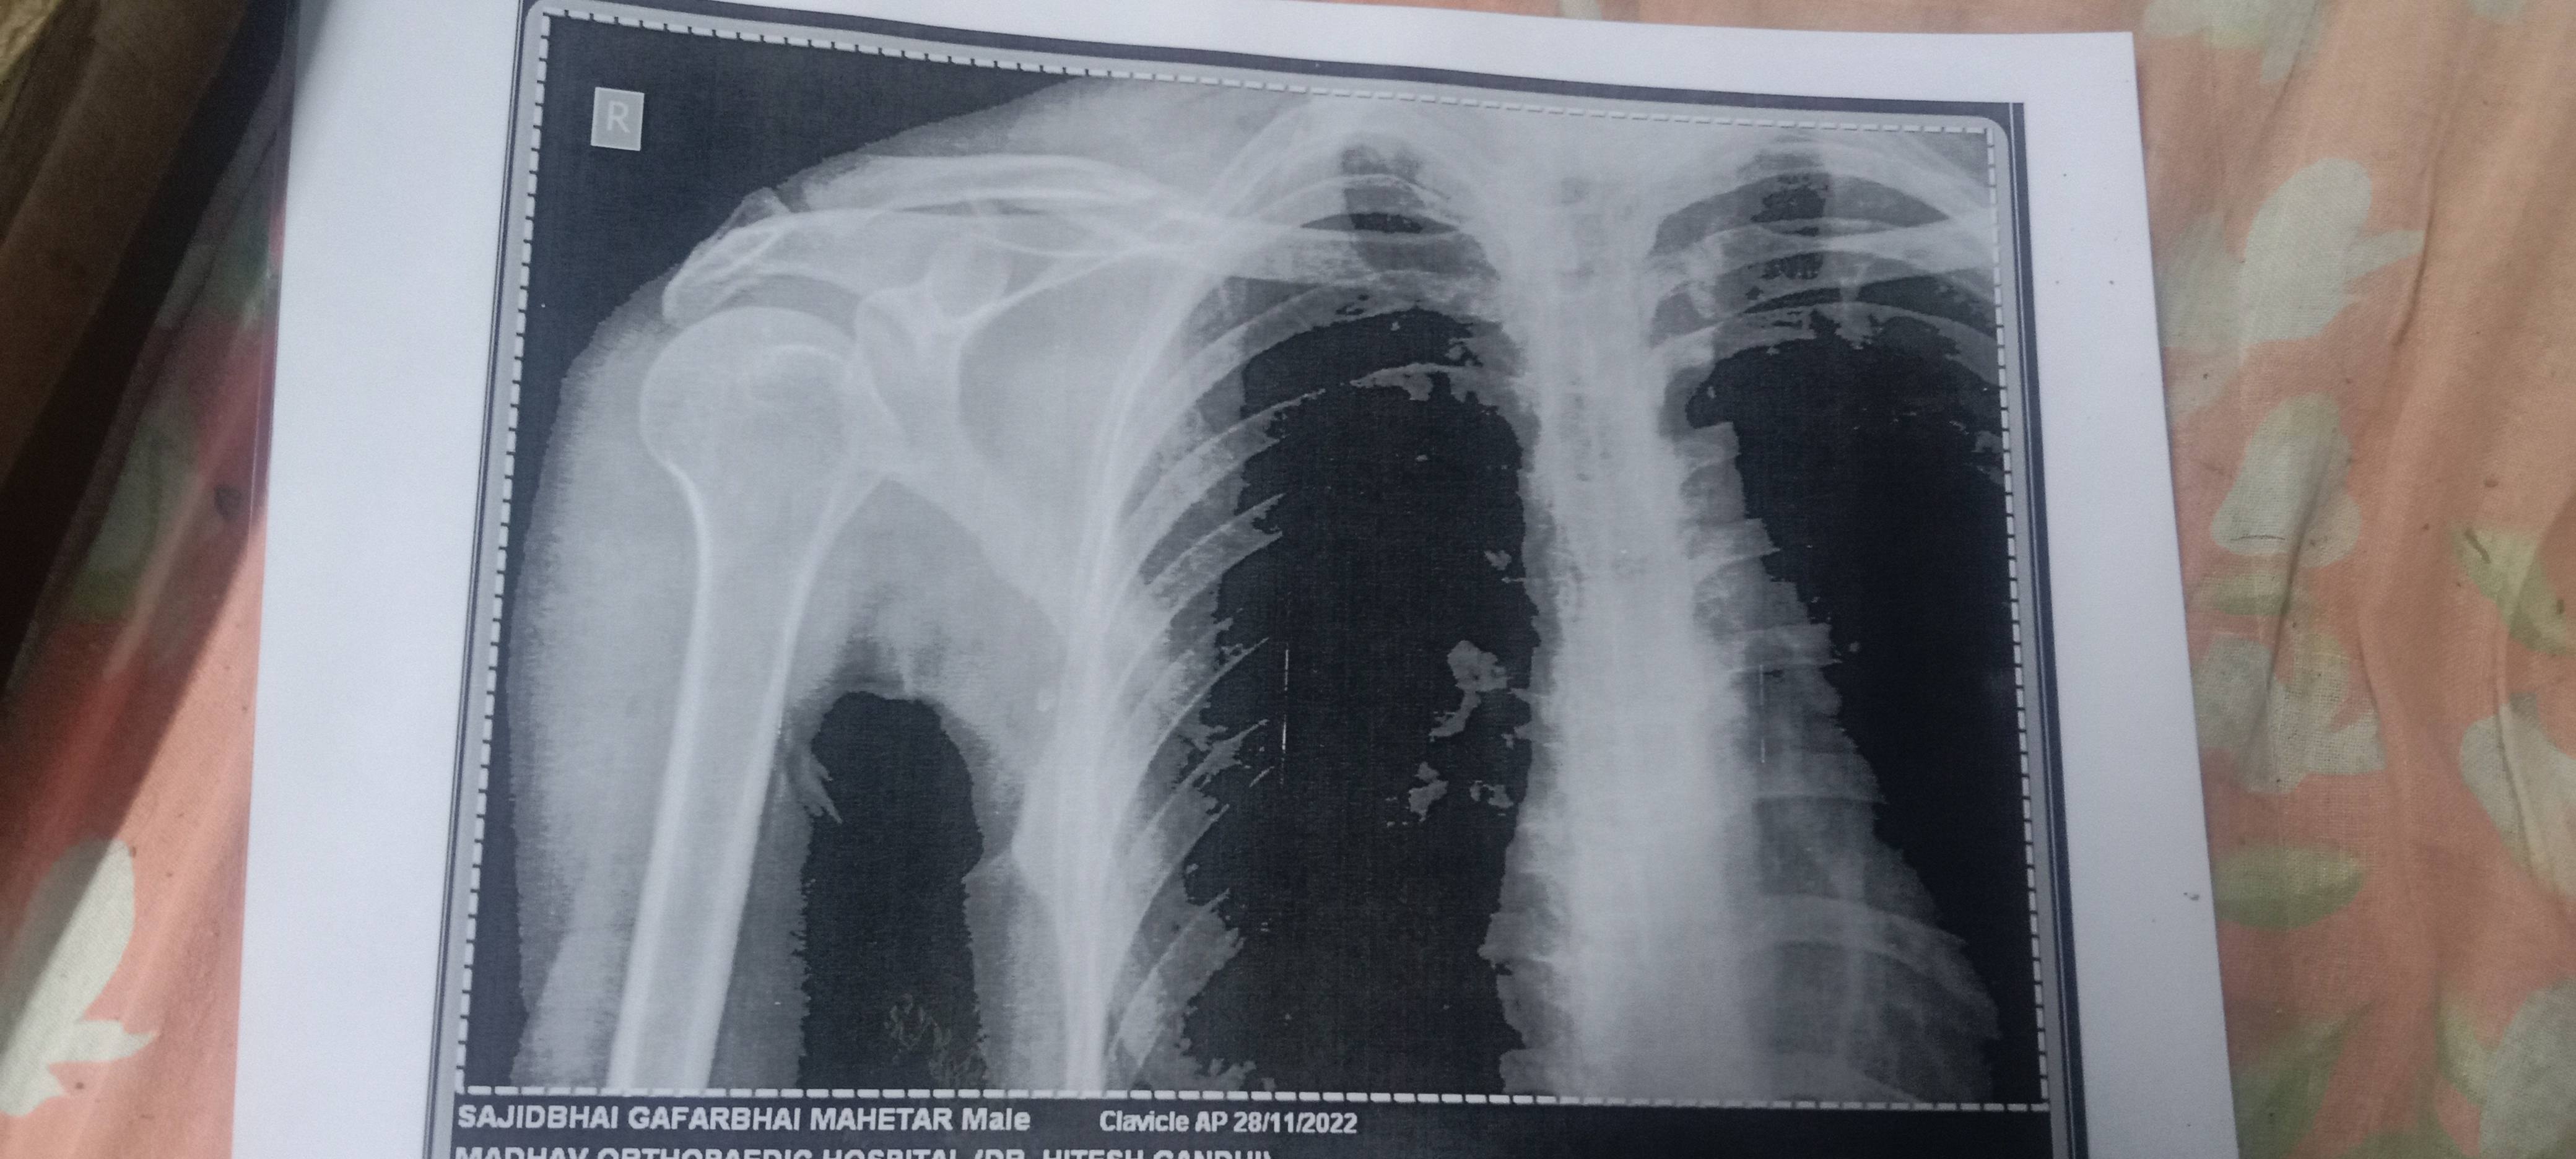

Sajid G metar

Sir aap itna bata do isme operation zaruri hai ya yese hi thik ho jayega patti se

Sir bina operation ke sahi ho jayega itna bata do plz